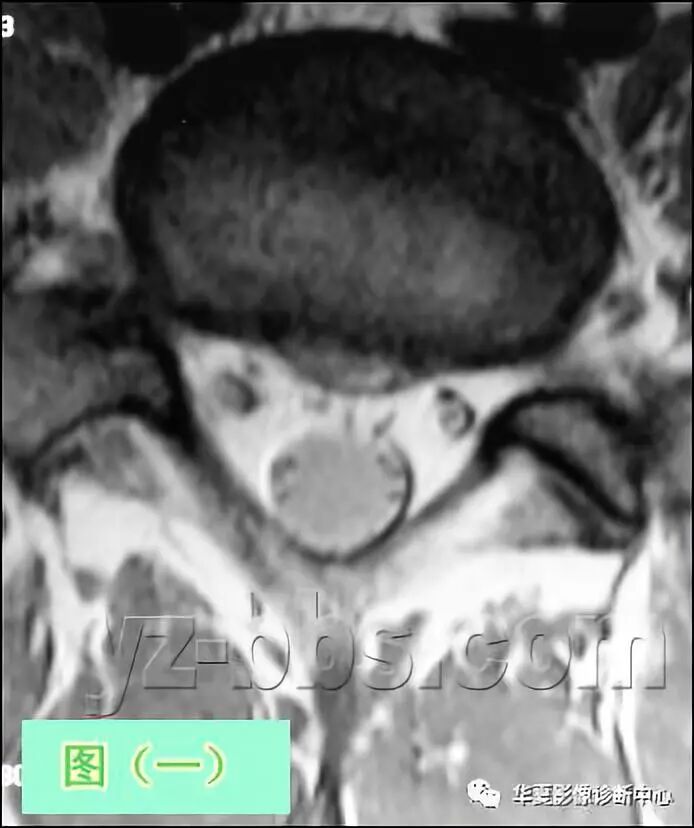

图(一)及图(二)是L5椎间盘的轴状面观

此病人虽有中等程度的腰椎间盘退变(在片子上看到黑色的椎间盘)和小的非压迫性4mm的中央型椎间盘突出,但他却有一个很大的“中央管”,可以很好地表现轴向核磁共振解剖。椎间盘的髓核在这两个图像中看不到,一是因为椎间盘脱水太严重,不能将纤维环及髓核区分开,另外这些图像为T1加权象(更高分辨率),所以不能将含水多的髓核与较干燥的纤维环区分开。但在一个正常的,非退化性椎间盘T2加权像上,很容易看清髓核区及纤椎环区T2加权图像(见图三)。

“后部神经结构”包括过往神经根(Traversing Nerve Roots)、硬膜囊(Thecal Sac)及发出神经根(Exiting Nerve Roots)。发出神经根位于椎间孔(看图中IVF粉红色区)内,在此图像中看不到。如果你发挥点想象力,你可以在图中找到一个象“米老鼠”样的图像,硬膜囊是米老鼠的头,两个过往神经根是米老鼠的耳朵。

再重复以下,虽然此椎间盘有4mm的突出,但此病人的过往神经根S1和突出物之间没有接触。 大部分情况下,椎间盘突出物或疤痕组织将遮挡住其中的一个过往神经根(米老鼠耳朵),这通常是神经根受压的象征。